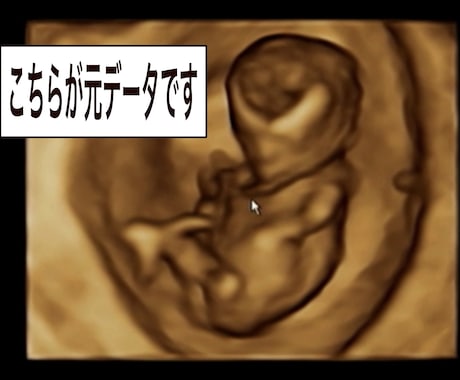

4Dエコーを自然に可愛く修正orイラスト化します 産婦人科専門医が4Dエコーをわかりやすく修正します。 イメージ1

妊婦健診の4Dエコー。やってみたら意外と可愛く見えない、なんならちょっと怖いかも… そんな経験はありませんか? ネットに出てくる4Dエコーはほんとに運良くいいタイミングで撮れたものがほとんどです。 赤ちゃんの動きだったり、臍の緒、胎盤などが邪魔をしてなかなか綺麗には写りません。 そもそも慣れていないとエコー画像の何が目で何が鼻かもわからないことも…。 そんな時にこのサービスに御依頼ください。 周産期新生児専門医、超音波専門医の私がエコーをわかりやすく修正、イラスト化します。 画像にあるように4Dエコーを自然に修正いたします。 輪郭強調やエコーで抜けてしまっているところの補正、目や鼻などをわかりやすく修正、邪魔な臍の緒や胎盤などの削除などなど 簡単なイラスト化にも対応いたします。 サンプルの週数、日付部分は希望があればお好きなコメントに変更可能です。 妊娠を頑張っている奥様へのプレゼントなどにいかがですか? 妊娠生活を少しでも楽しく過ごして頂けれたら幸いです。